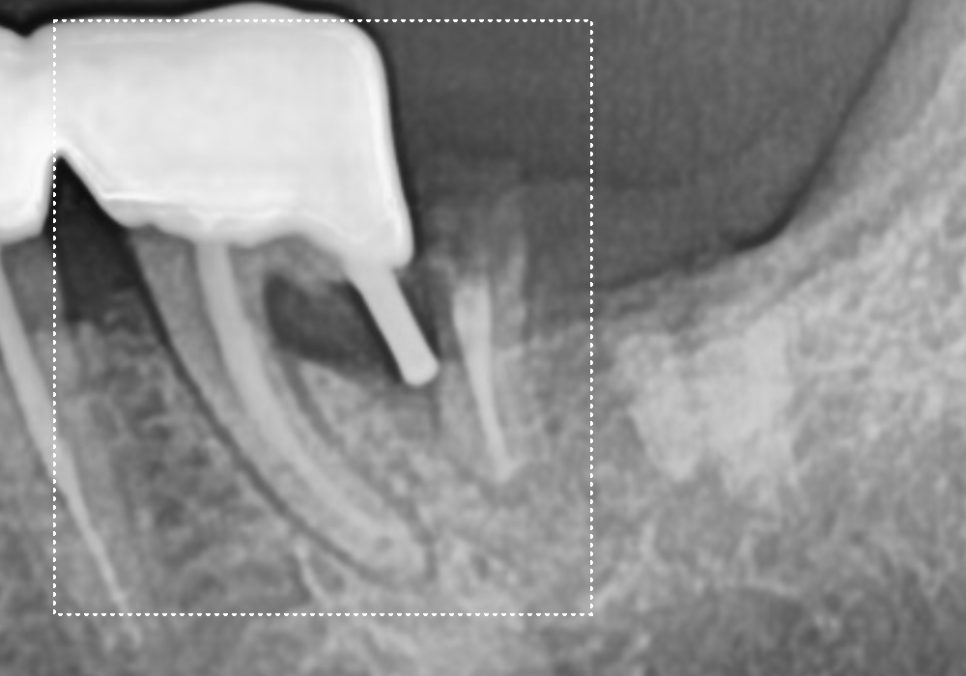

CT를 살펴볼게요~

241015

혹시 앞서 보여드렸던 환자와의

차이점을 눈치채셨나요?

빨간 동그라미로 표시한 하치조 신경인데요.

이 신경과 뿌리 끝 사이의 뼈가

확실히 뼈가 꽉 차 있고

하얗게 밀도가 높은 느낌이 들죠~?

이 환자분은 뿌리 끝에 염증이

있었던 게 아니라,

치아 자체가 약해 뿌리만 부러진 상태였기에

주변 뼈는 아주 건강하게 남아 있었습니다.

이렇게 토대가 튼튼하다면

치아를 뽑는 당일 임플란트를 바로 심을 수 있어요.